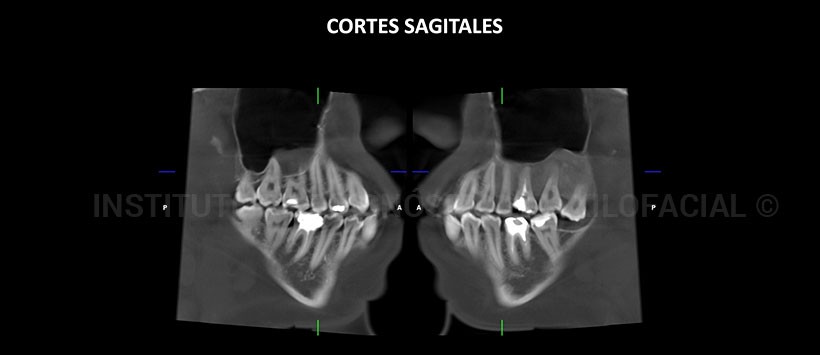

A la evaluación de la tomografía volumétrica (CBCT) cortes axiales (Figura 2), coronales (Figura 3), sagitales (Figura 4) y transaxiales (Figura 5), se aprecia aumento de volumen con alteración del patrón óseo en la región posterior del maxilar superior izquierdo que se extiende de mesial de pieza 24 hasta la región de la tuberosidad del maxilar, caracterizado por un aumento de la densidad ósea con apariencia de “vidrio esmerilado”, ocasiona expansión de las tablas óseas, de la cima del reborde alveolar y del piso del seno maxilar.